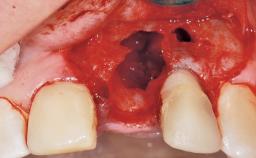

Late Placement of an Implant in a Maxillary Left Central Incisor Site

A 30-year-old female patient had lost tooth 21 and was referred to our clinic for consultation and treatment. Due to advanced apical infection, tooth 21 had been extracted two months earlier at another clinic and an acrylic-resin tooth had been bonded to the adjacent teeth. The patient desired implant treatment to avoid any damage to the adjacent natural teeth. While the patient had no history of any systemic disorder, she was a heavy smoker and exhibited medium to advanced periodontitis in the entire jaw. After the initial treatment to achieve a pocket probing depth of less than 4 mm and no bleeding on probing, a decrease in the height of the papillae mesial and distal to the extraction site and overall gingival recession were observed.

Bone Augmentation Horizontal|Staged

Bone Volume Deficient horizontally, requiring prior grafting